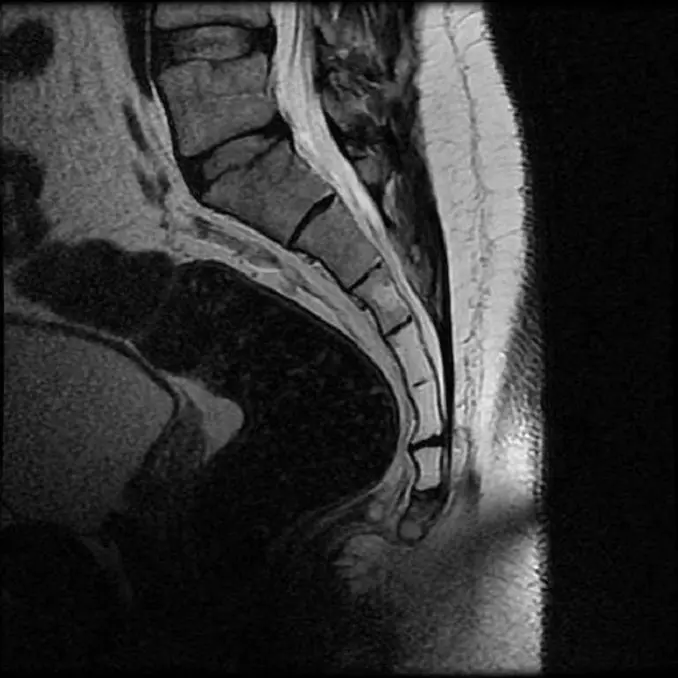

Рентгеновские снимки крестцово-копчикового отдела позвоночника